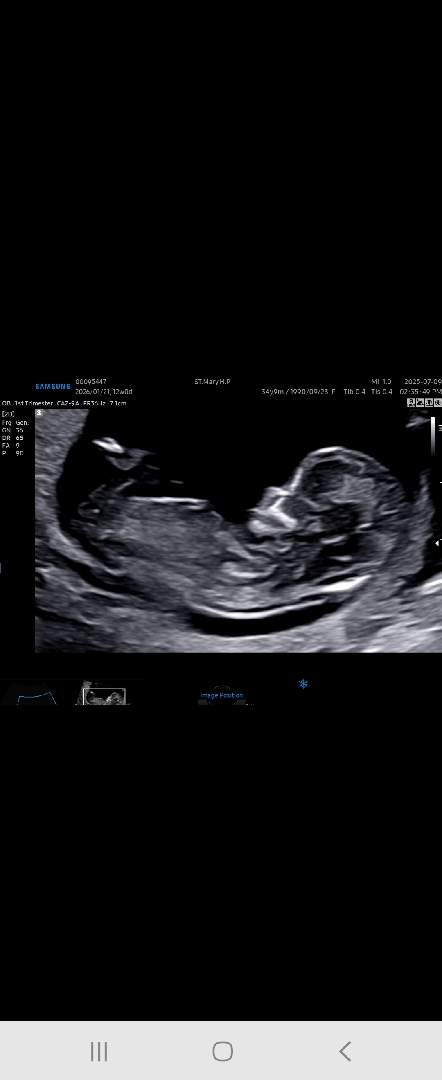

12주 각도법! 쌍둥이중 첫째😁

12주 입초보고 왔는데 딸일까 아들일까?